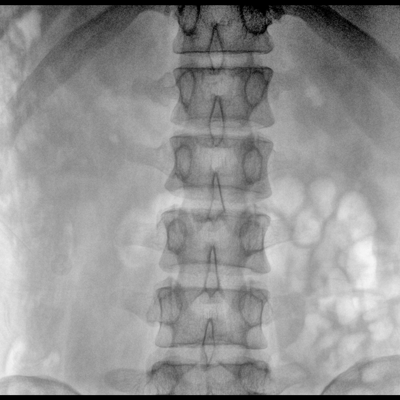

大尺寸液晶顯示器,圖像顯示清晰細(xì)膩;顯示器可大角度旋轉(zhuǎn),滿足臨床多角度觀察圖像的需要。

在球管和平板探測器兩端,分別加裝了激光定位系統(tǒng),滿足不同擺位無射線下的定位需求,降低醫(yī)患輻射劑量的同時,提高臨床工作效率。

具備束光器預(yù)覽功能,可以在無射線狀態(tài)下,實現(xiàn)曝光范圍大小的調(diào)節(jié);大幅減少臨床反復(fù)曝光帶來的射線輻射;并自動調(diào)整圖像興趣區(qū)大小與位置,使自動模式更準(zhǔn)確。

DAP劑量顯示可以在使用機器的過程中,直接觀察到劑量顯示,保障醫(yī)患健康。